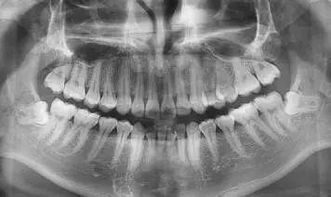

1.拔牙后吃什么食物好